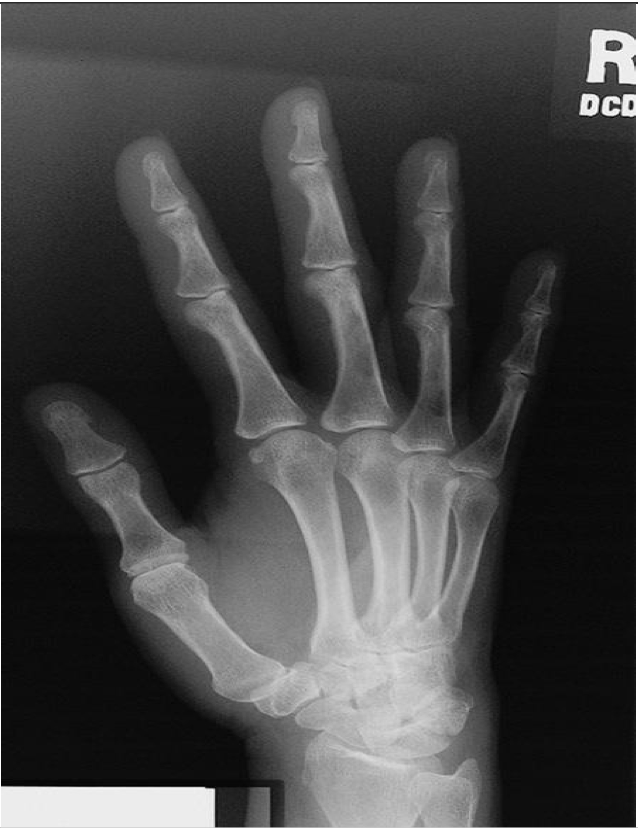

PA Hand

Evaluation Criteria for PA Hand

• Entire hand and carpals demonstrated

• Center of field at 3rd MCP joint

• MCP and IP joints are open

• Equal concavity of phalanges and metacarpals

• Slight overlap of bases of the 2nd to 5th metacarpals

• No overlap of heads of the 2nd to 5th metacarpals

• Minimum of 2.5cm (1”) of radius & ulna included